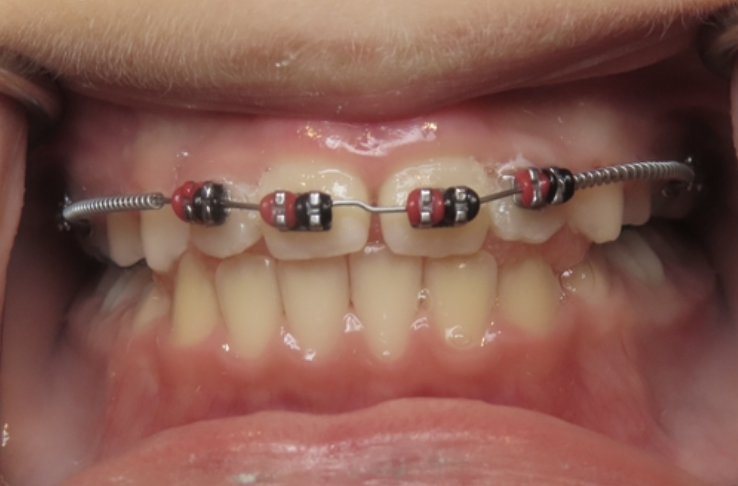

Protrusion

Upper teeth stick out beyond the lower teeth.